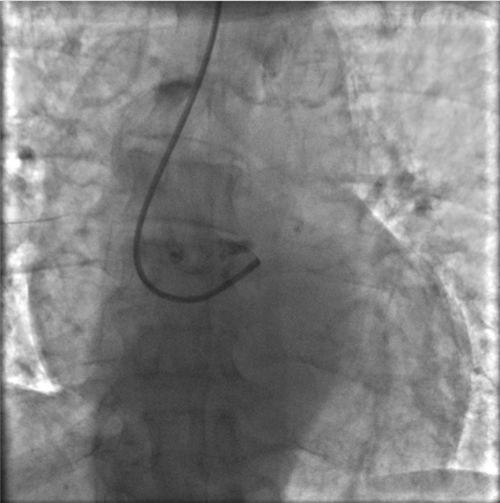

左主干完全閉塞

小心操作導絲及導管,艱難到達主動脈根部,但導管難以“到位”左冠口,“冒煙”見左主干居然完全閉塞了。